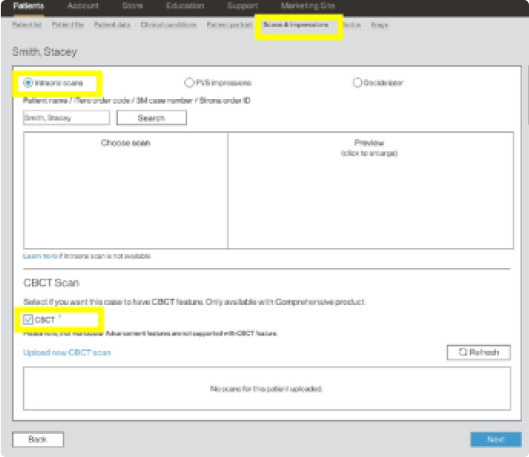

Enable CBCT functionality in ClinCheck Pro in 4 easy steps to work in one integrated platform.

Step 1

When submitting a case, on the “Scan’s & Impressions” tab check “CBCT” in the CBCT Scan section.

Step 1

When submitting a case, on the “Scan’s & Impressions” tab check “CBCT” in the CBCT Scan section.